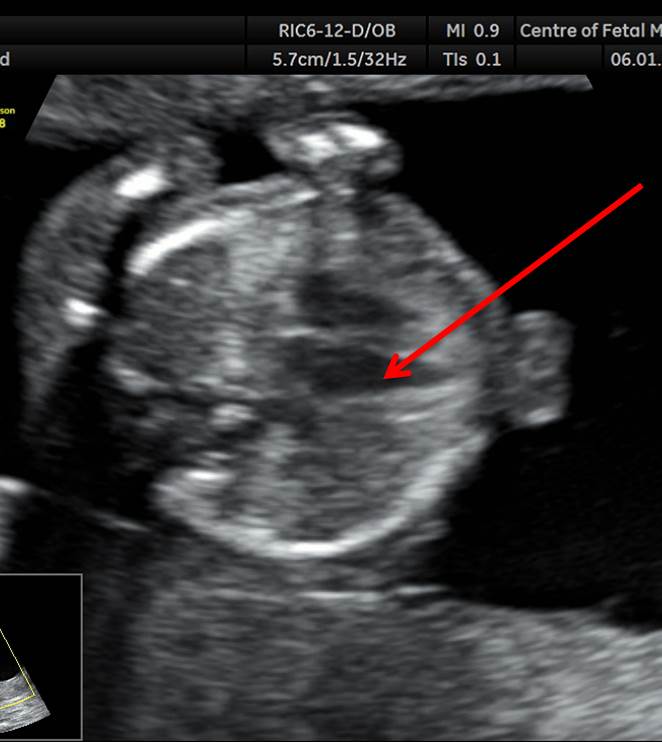

Вопрос 9

1-9.jpg

Какая структура указана стрелкой?

• А — норма;​

• Б — ДМЖП;​

• В — атрезия митрального клапана;

• Г — АВ-канал

Ответ на вопрос 9